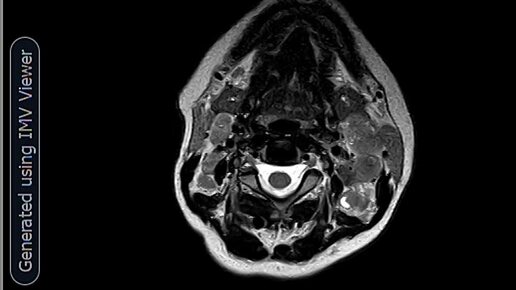

МРТ-Метастазы в лимфоузлы шеи